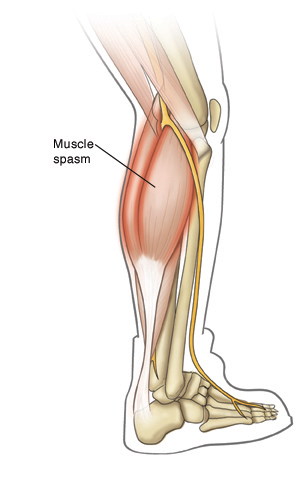

Muscle Spasm

A muscle spasm (also called a cramp) is an involuntary muscle contraction. The muscle or muscle group tightens quickly and strongly. A hard lump may form in the muscle. Muscle spasms can be very painful. Here's how to treat and prevent muscle spasms.